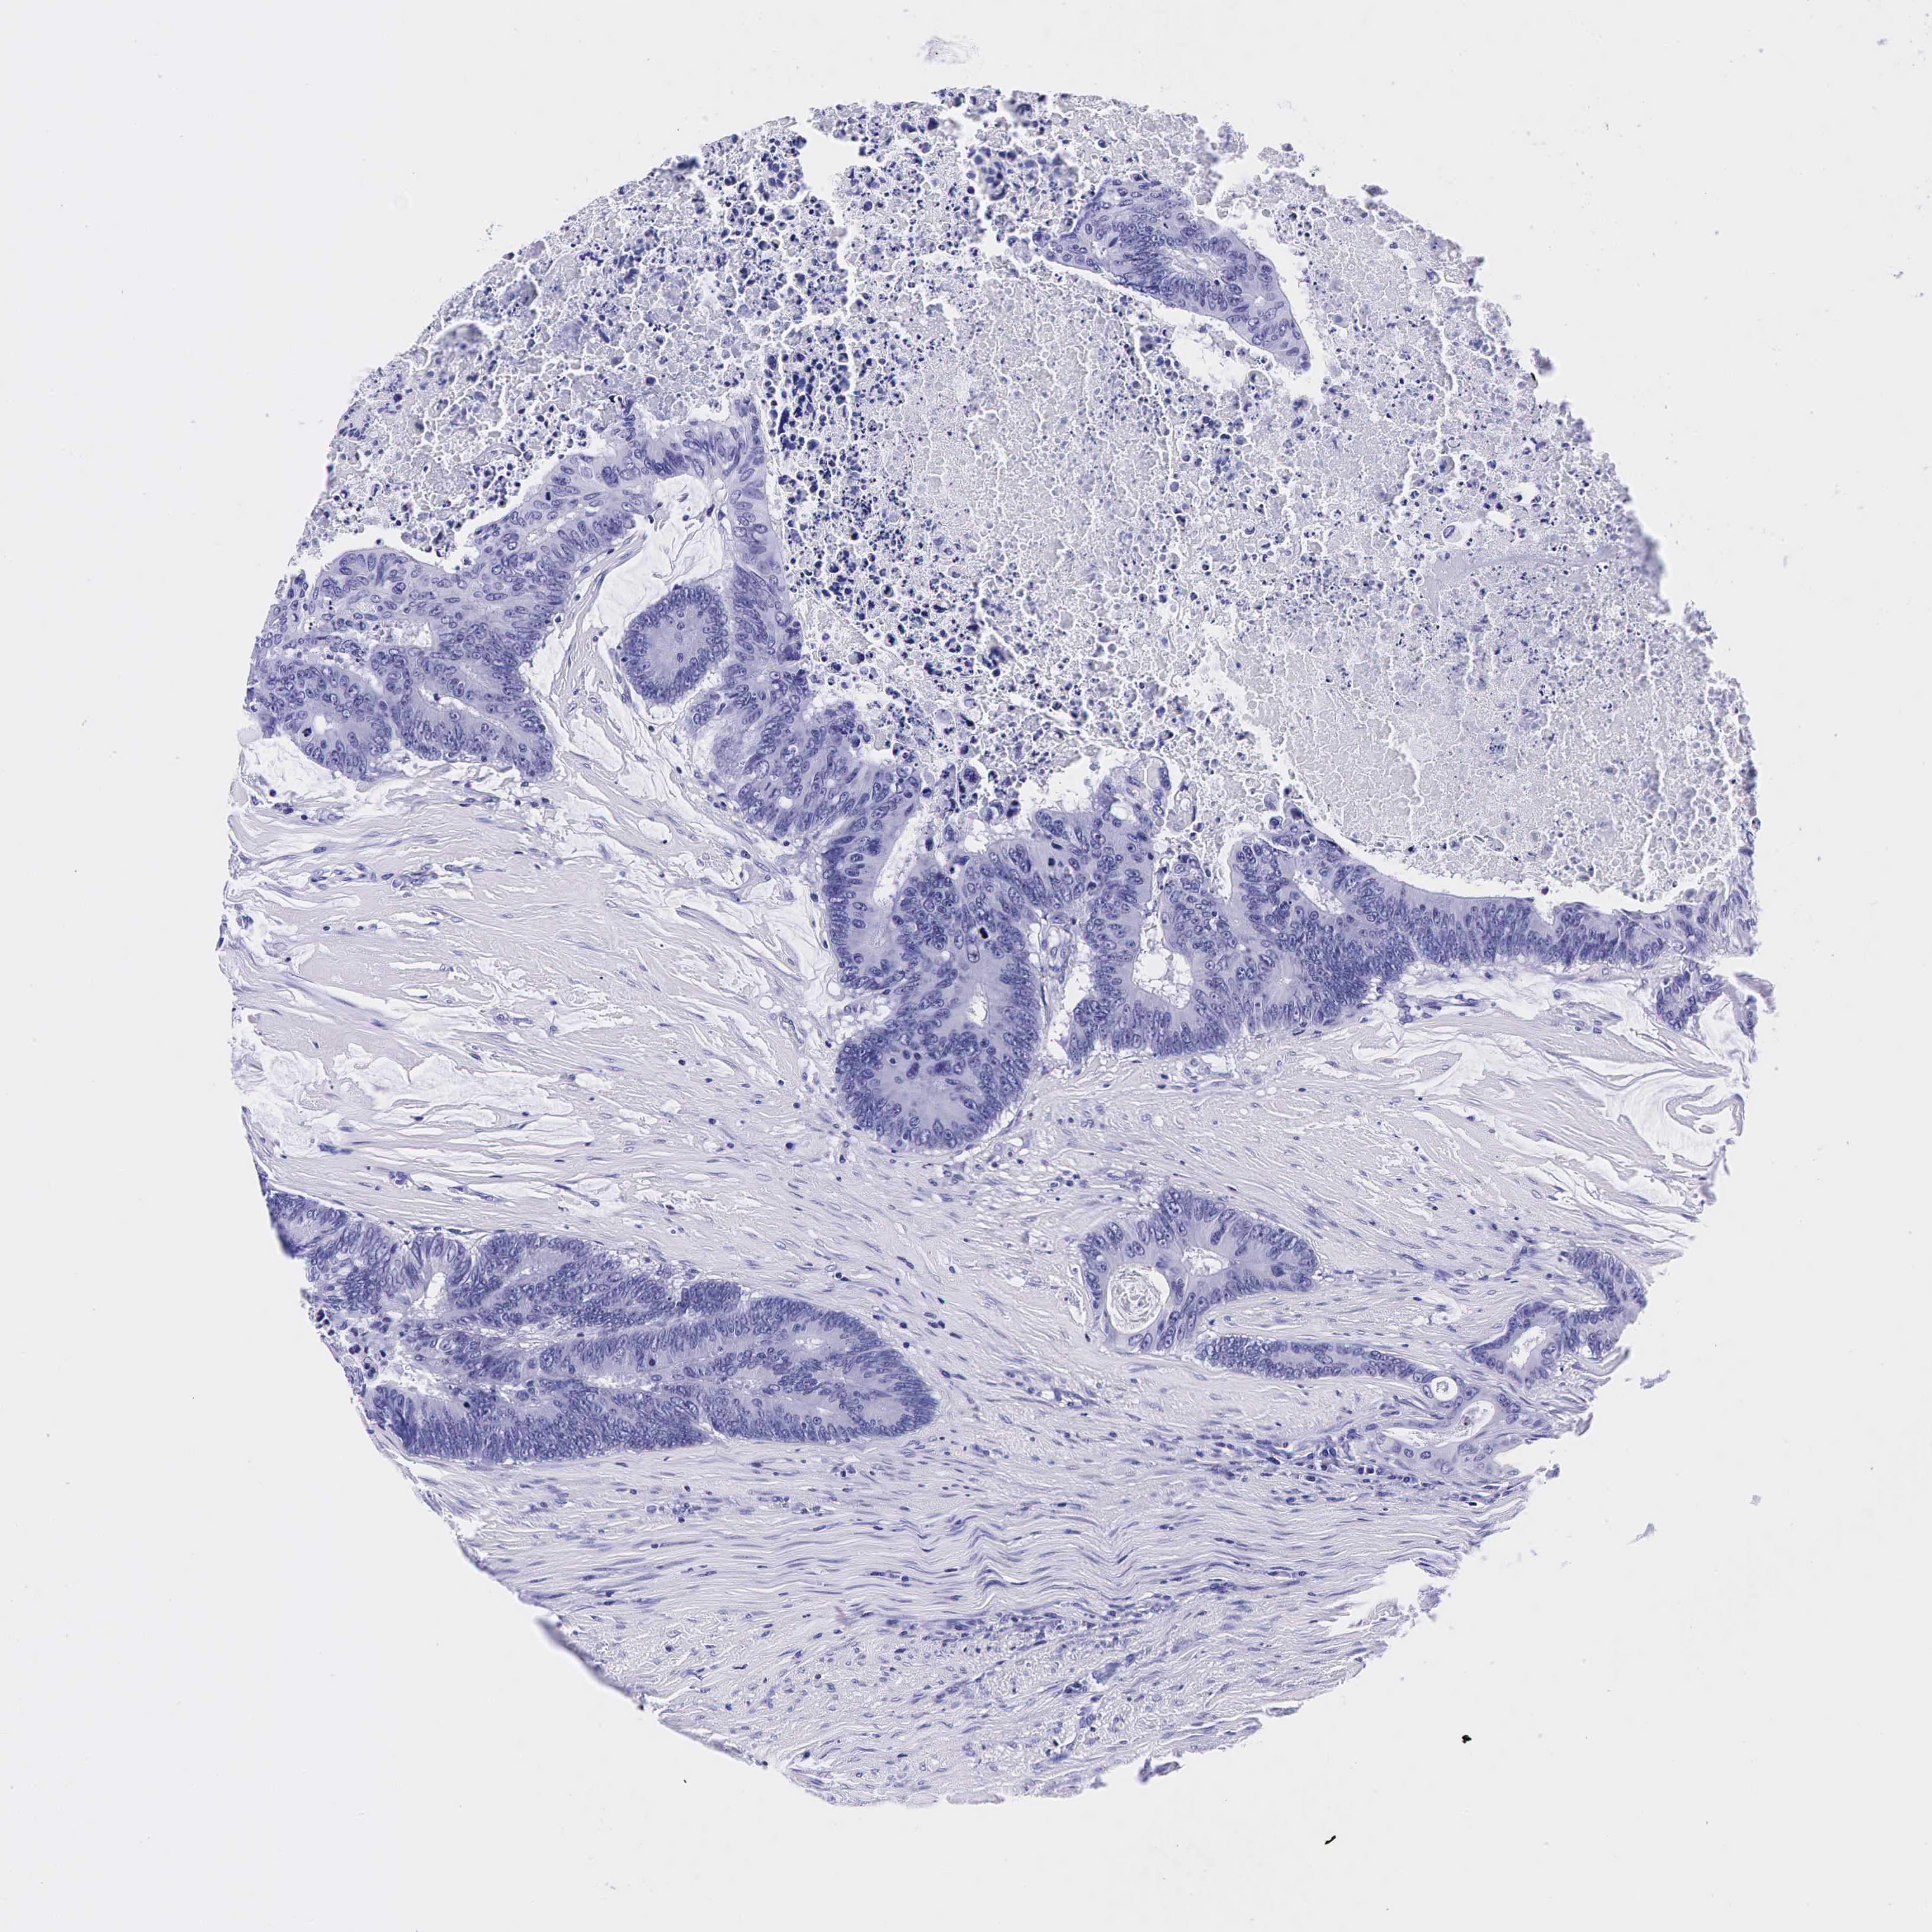

Colorectal cancer

Human cancer

Colon adenocarcinoma